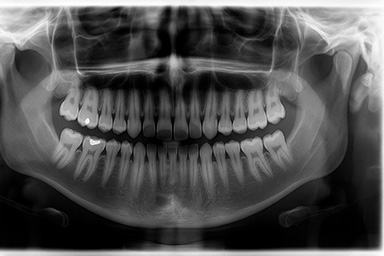

Radiografía panorámica ejemplo

La radiografía panorámica dental ofrece una visión completa de los maxilares, dientes, articulación temporomandibular (ATM) y senos maxilares en una sola toma. Es clave para diagnósticos integrales en ortodoncia, cirugía bucal y tratamientos complejos.